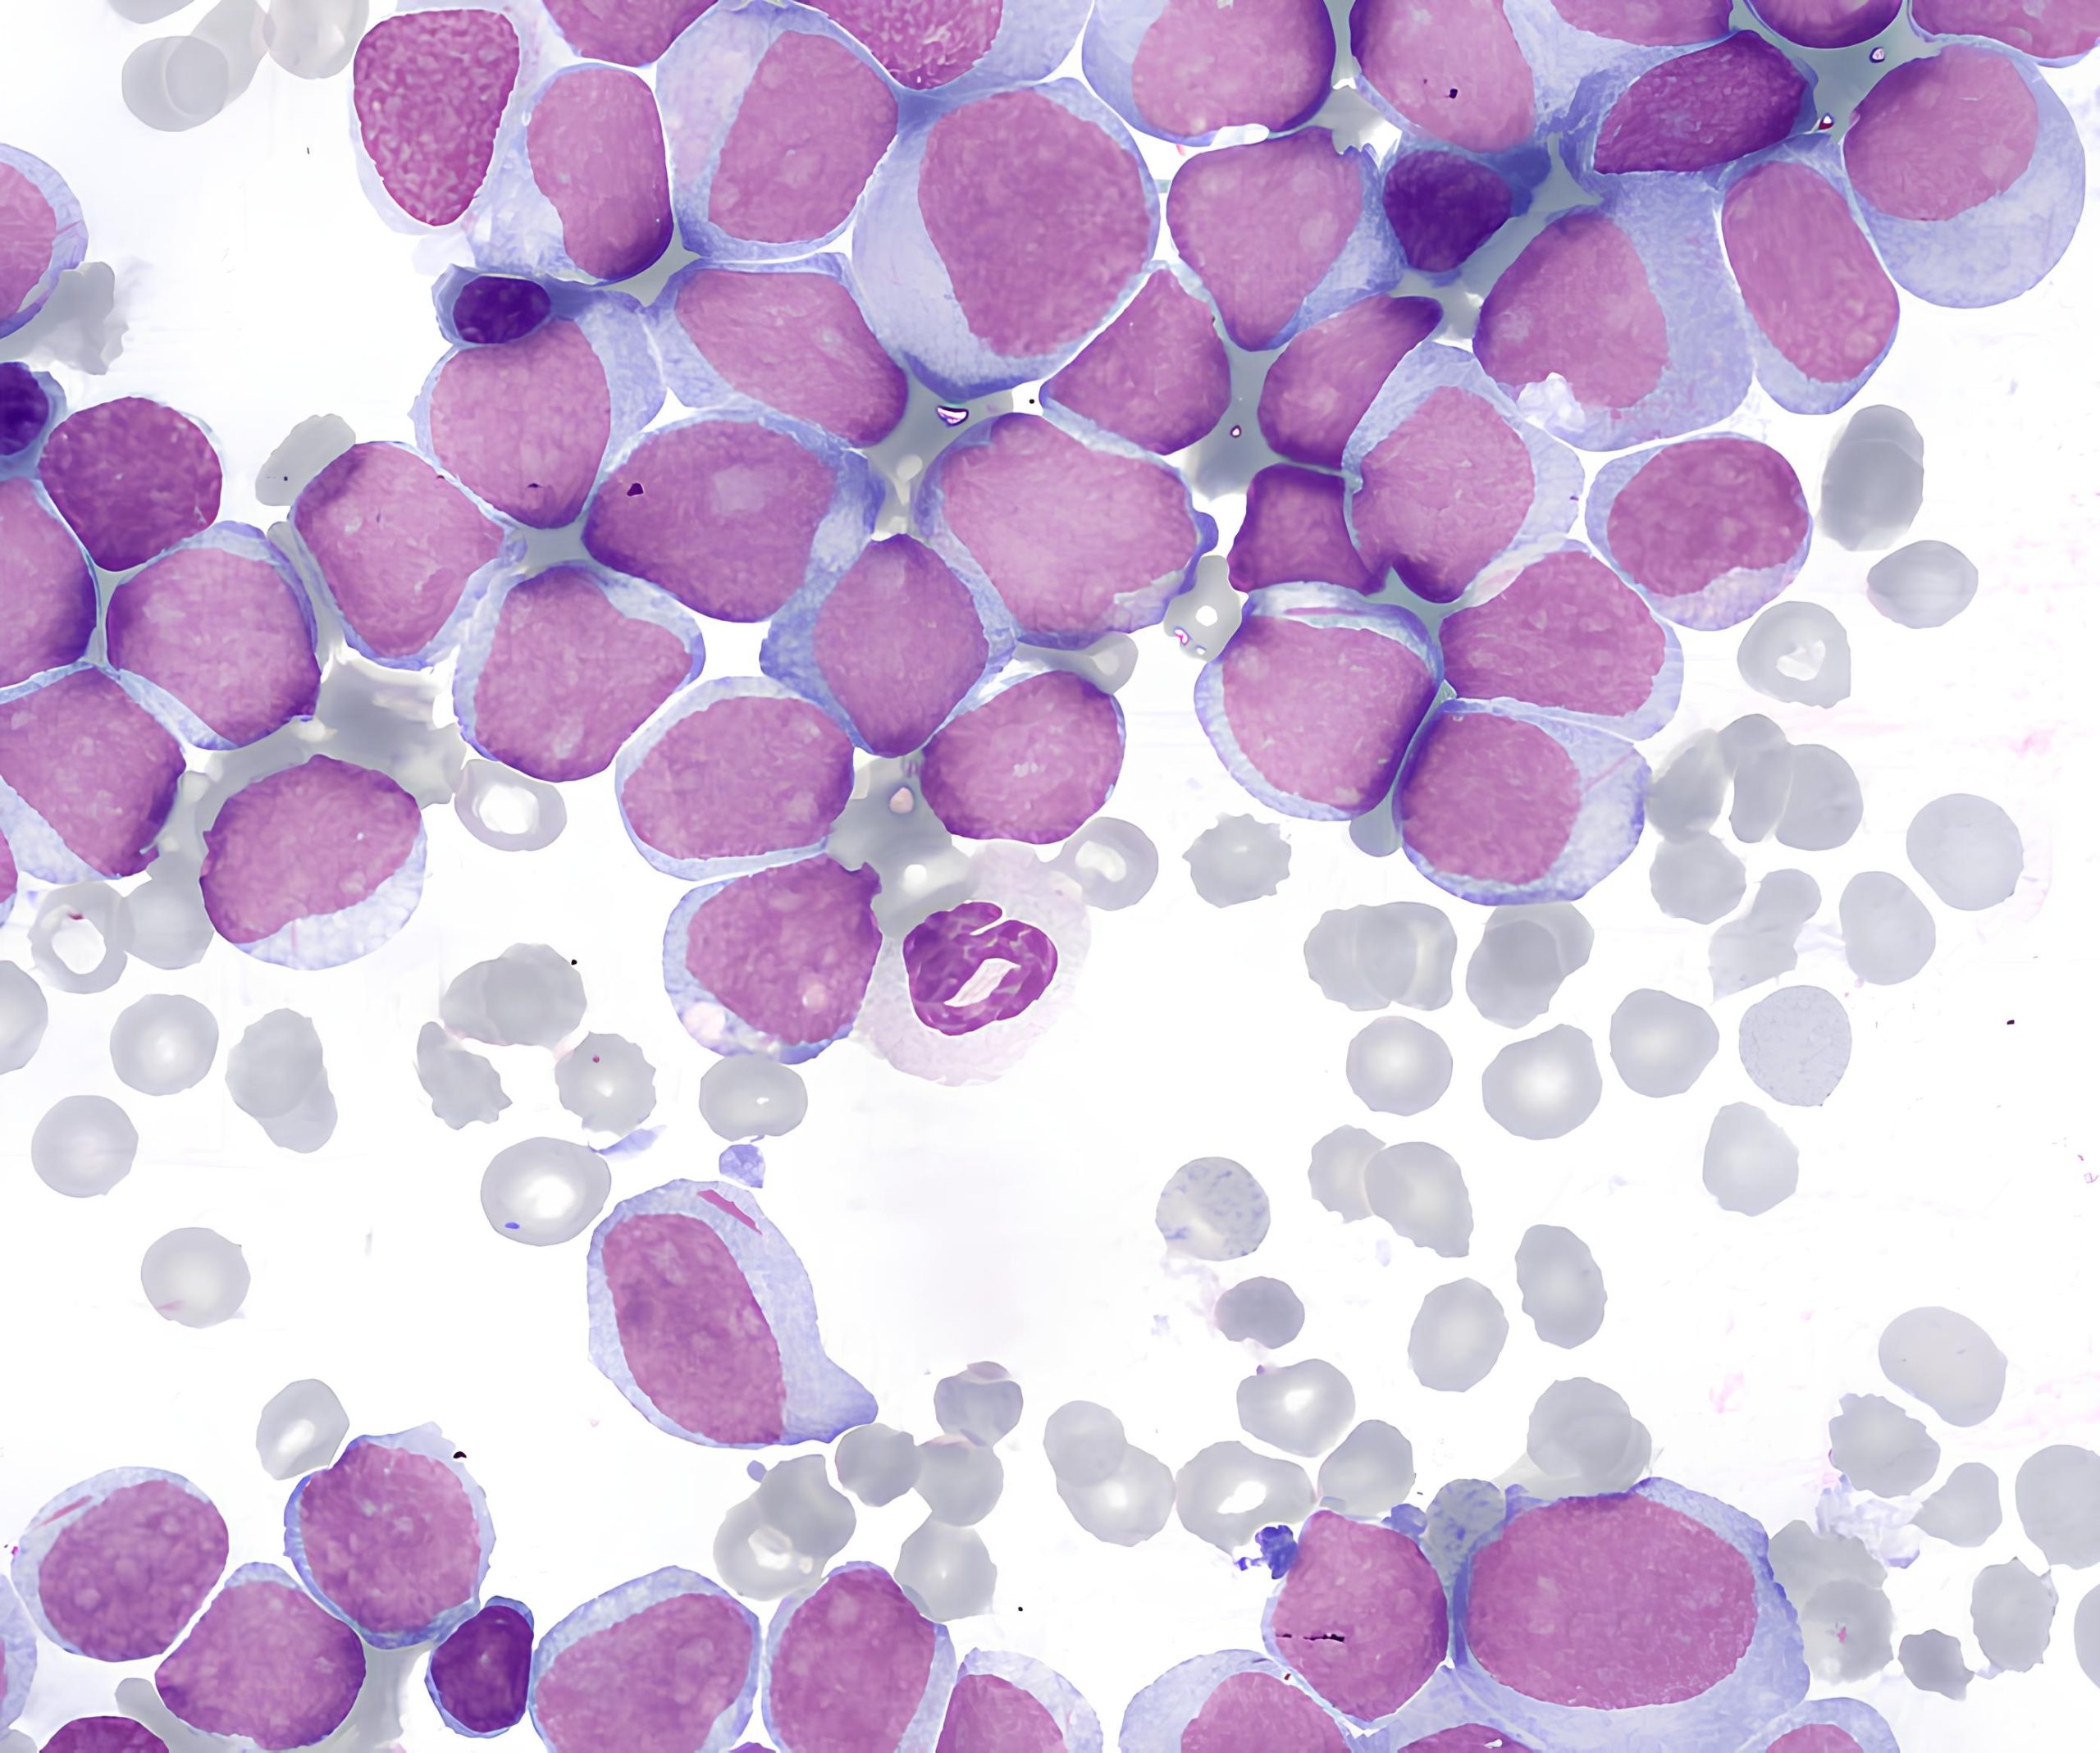

Bệnh bạch cầu cấp dòng tủy (Acute Myeloid Leukemia – AML) là một dạng ung thư máu ác tính phát sinh từ tế bào gốc tạo máu của dòng tủy (myeloid) trong tủy xương. Bệnh đặc trưng bởi sự tăng sinh bất thường của các tế bào non (blast) dòng tủy và sự ức chế sinh máu bình thường, dẫn đến thiếu máu, giảm tiểu cầu và giảm bạch cầu chức năng.

- Công thức máu: giảm hồng cầu, giảm tiểu cầu, tăng hoặc giảm bạch cầu, có thể thấy blast ngoại vi.

- Tủy đồ: xác định tỉ lệ blast và hình thái bất thường dòng tủy.

- Flow cytometry: khẳng định nguồn gốc dòng tủy qua các dấu ấn như CD13, CD33, MPO, CD117…